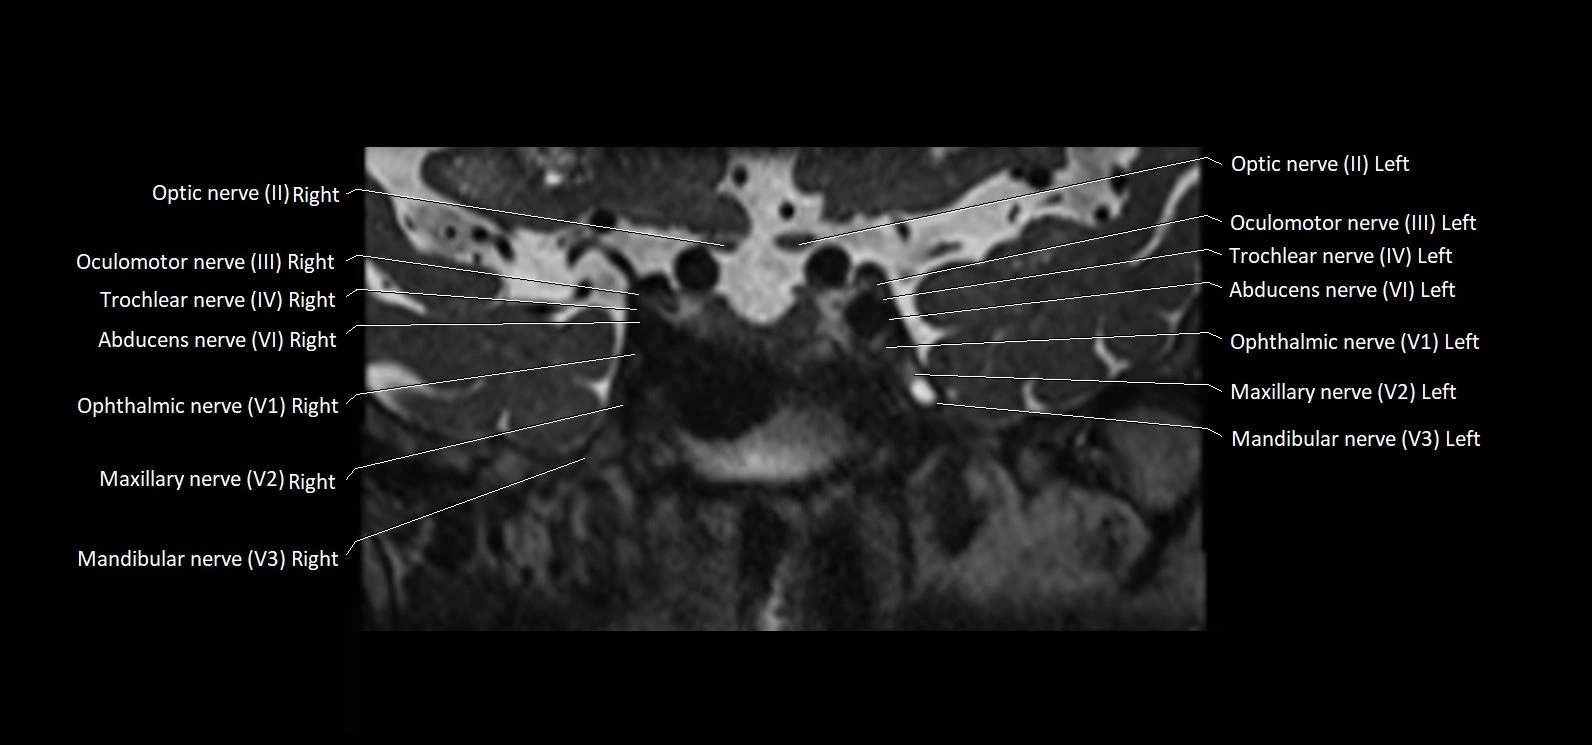

MRI Appearance

• The abducens nerve is a small, thin, linear structure

• Best visualized on high-resolution T2-weighted 3D MRI sequences (e.g., FIESTA or CISS)

• Seen as a hypointense (dark) line running from the brainstem at the pontomedullary junction, traversing the prepontine cistern, and entering Dorello’s canal under the petrosphenoidal ligament, then into the cavernous sinus, and finally the orbit

• May be challenging to visualize in standard MRI due to its small size

• Pathology may be inferred by absence, displacement, or enhancement of the nerve